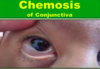

Presentation: headache, chemosis, oedema of eyelids, proptosis, painful opthalmoplegia, fever